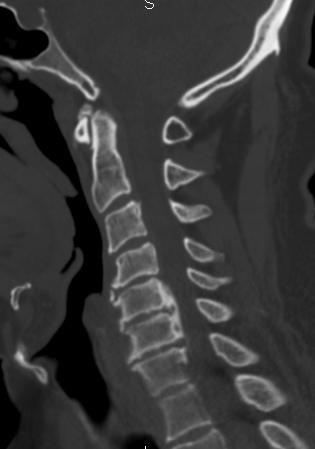

9. A 67-year-old man falls forward from standing height sustaining a hyperextension injury to his neck. He has neurological deficits present on physical examination. A radiograph, CT scan and MRI are seen in Figures A, B and C. Which of the following MOST likely characterizes his neurologic examination?"

FIGURES: A

B

C

DISCUSSION: The patient in the scenario has a central cord syndrome. The images show a relatively kyphotic spine with moderate osteophyte formation from C4 through C6. The MRI shows stenosis without cord signal change. Central cord syndrome is characterized by motor deficits more pronounced in the upper extremities than lower extremities. In addition, finger and wrist motor function is more affected than shoulder and biceps function. Sensory deficits are usually minimal.